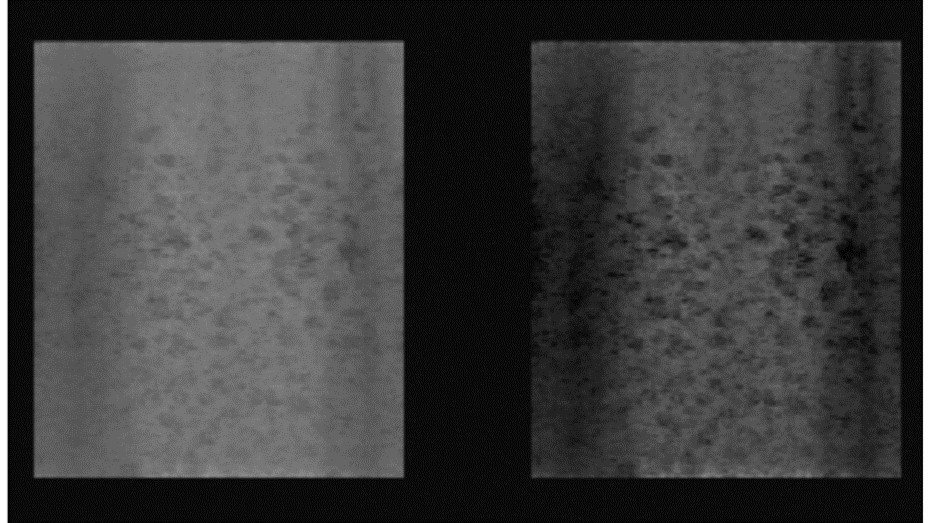

Figure 4.Random Void Phantom - medium contrast resolution (21.61 dB, Alloca SSD 5412). Original 3D rendered image (left), with increased image contrast (right).

Random Void Phantom - medium contrast resolution (21.61 dB, Alloca SSD 5412).             Original 3D rendered image (left), with increased image contrast (right).